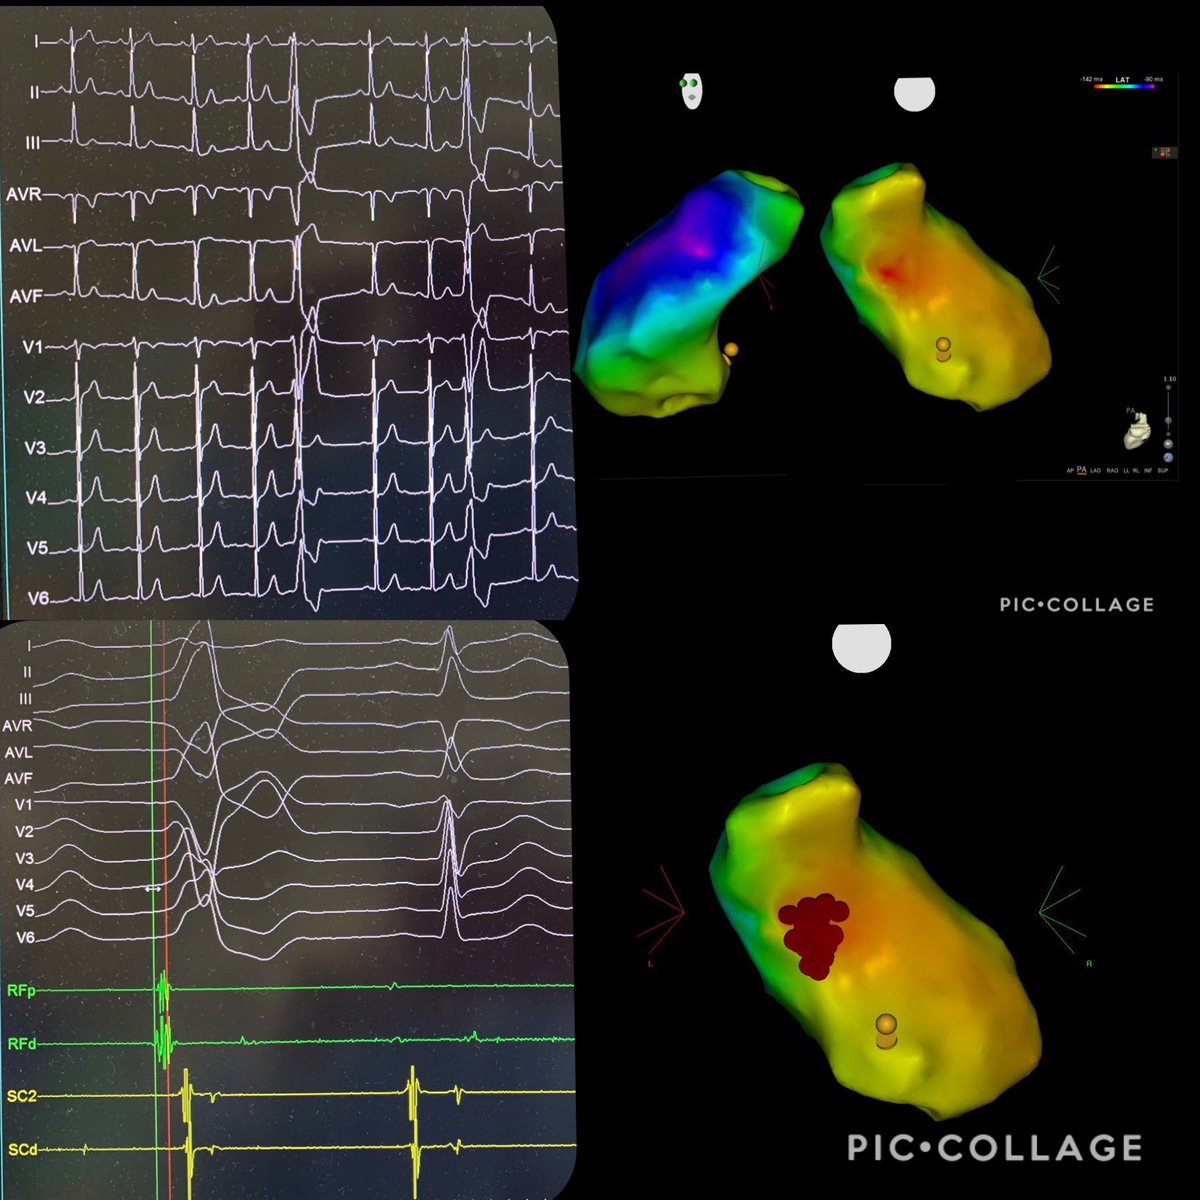

PVC ablation! first mapping RVOT with good precocity but failure.

#EPeeps

#cardiotwitter

#CardioEd